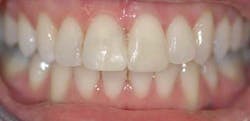

Some patients want a nicer smile and to get that smile we have to level the teeth, straighten the arch, or close diastemas.

Once we got the word out that we were offering this simple solution, our patients began asking about it. It does not take much to get them going since we can offer them the solution they’ve been seeking. The conservative Cfast approach is quick, easy, and offers a win-win solution to many of my esthetic-restorative challenges.